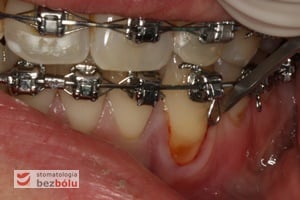

- Efekt leczenia ortodontycznego (np. podczas przesuwania przedsionkowego zębów)

- Długo utrzymujący się stan zapalny wokół szyjki zęba